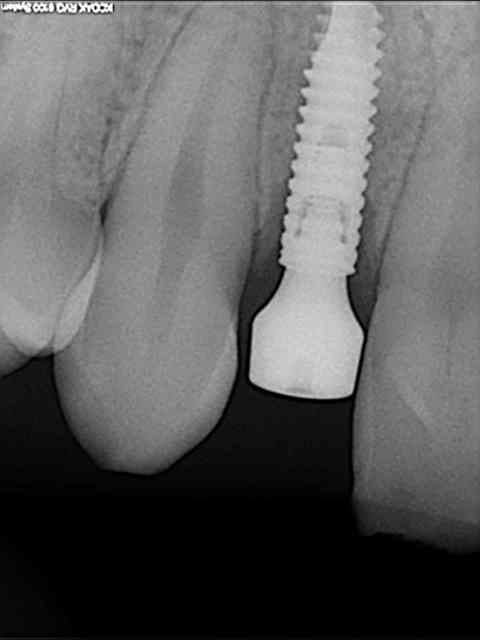

je reviens sur ce cas que j'ai un peu délaissé...

-cicatrisation

-mise en place vis de cica petit diamètre

-ensuite on augmente le diamètre en conservant et en gonflant les tissus gingivaux

R12 kfzljk - Eugenol